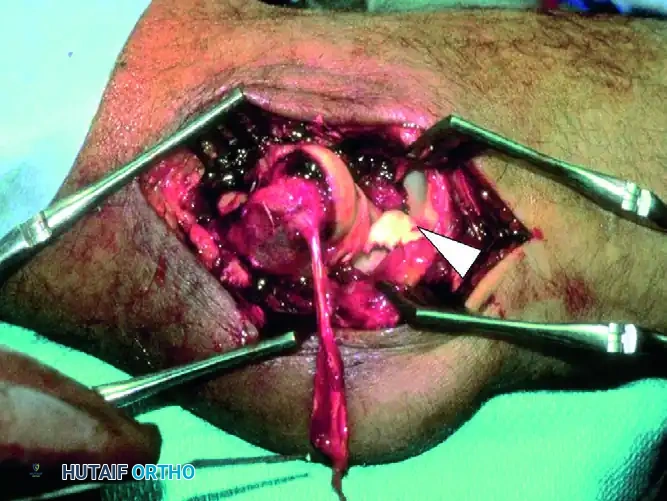

FIGURE 57-66 A: Intraoperative view of a “terrible triad” injury. Note the characteristic stripping of the lateral collateral ligament complex from the distal humerus. A portion of the common extensor origin/lateral ligament complex is hanging down from the bare lateral condyle. The coronoid fragment is trapped in the joint (arrowhead), and the defect in the radial head can be seen behind it.

The joint is irrigated, and fracture hematoma is cleared. If the radial head is irreparably comminuted, it is excised at this stage. Crucially, the radial head prosthesis is not inserted yet. The void left by the excised radial head provides unparalleled visualization of the deep, anteriorly located coronoid process.